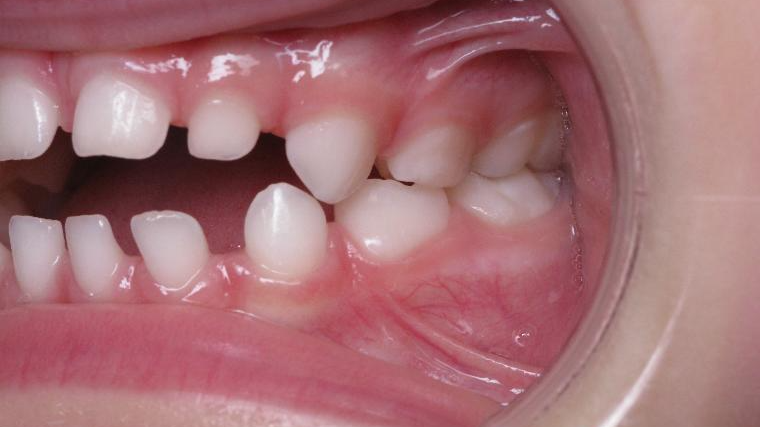

12 béance inversé droit 4 ans

inversion postérieur coté droit et espace entre les dents du haut et du bas (diastèmes)